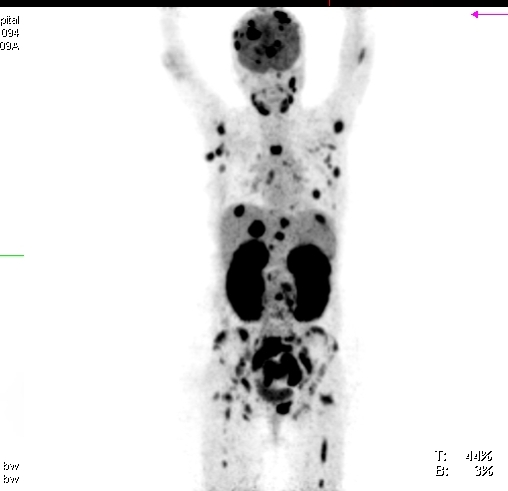

Recent literature evidence has demonstrated a small but definite increase in the risk of malignancies in SLE patients when compared to general population. The present case study reports a rare occurrence of Burkitt’s lymphoma in a 32-year-old female patient who had been diagnosed with SLE around 3 years ago. The study also discusses the possible pathophysiological links between Burkitt’s lymphoma and SLE.